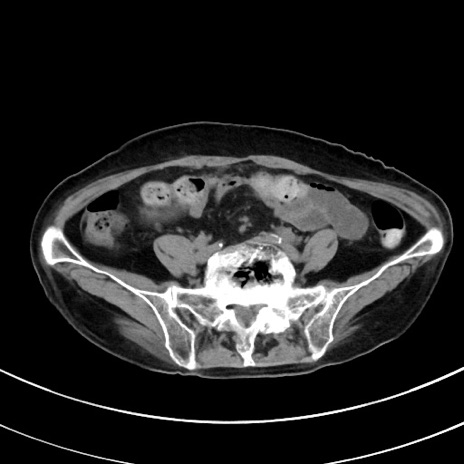

症例33(横断像)

【症例】70歳代 女性

【主訴】心窩部痛

【現病歴】延髄病変の精査・加療にて神経内科入院中。本日より心窩部痛あり。

【既往歴】虫垂炎

【身体所見】右下腹部を中心に圧痛と反跳痛あり。

【データ】WBC 10900、CRP 0.02